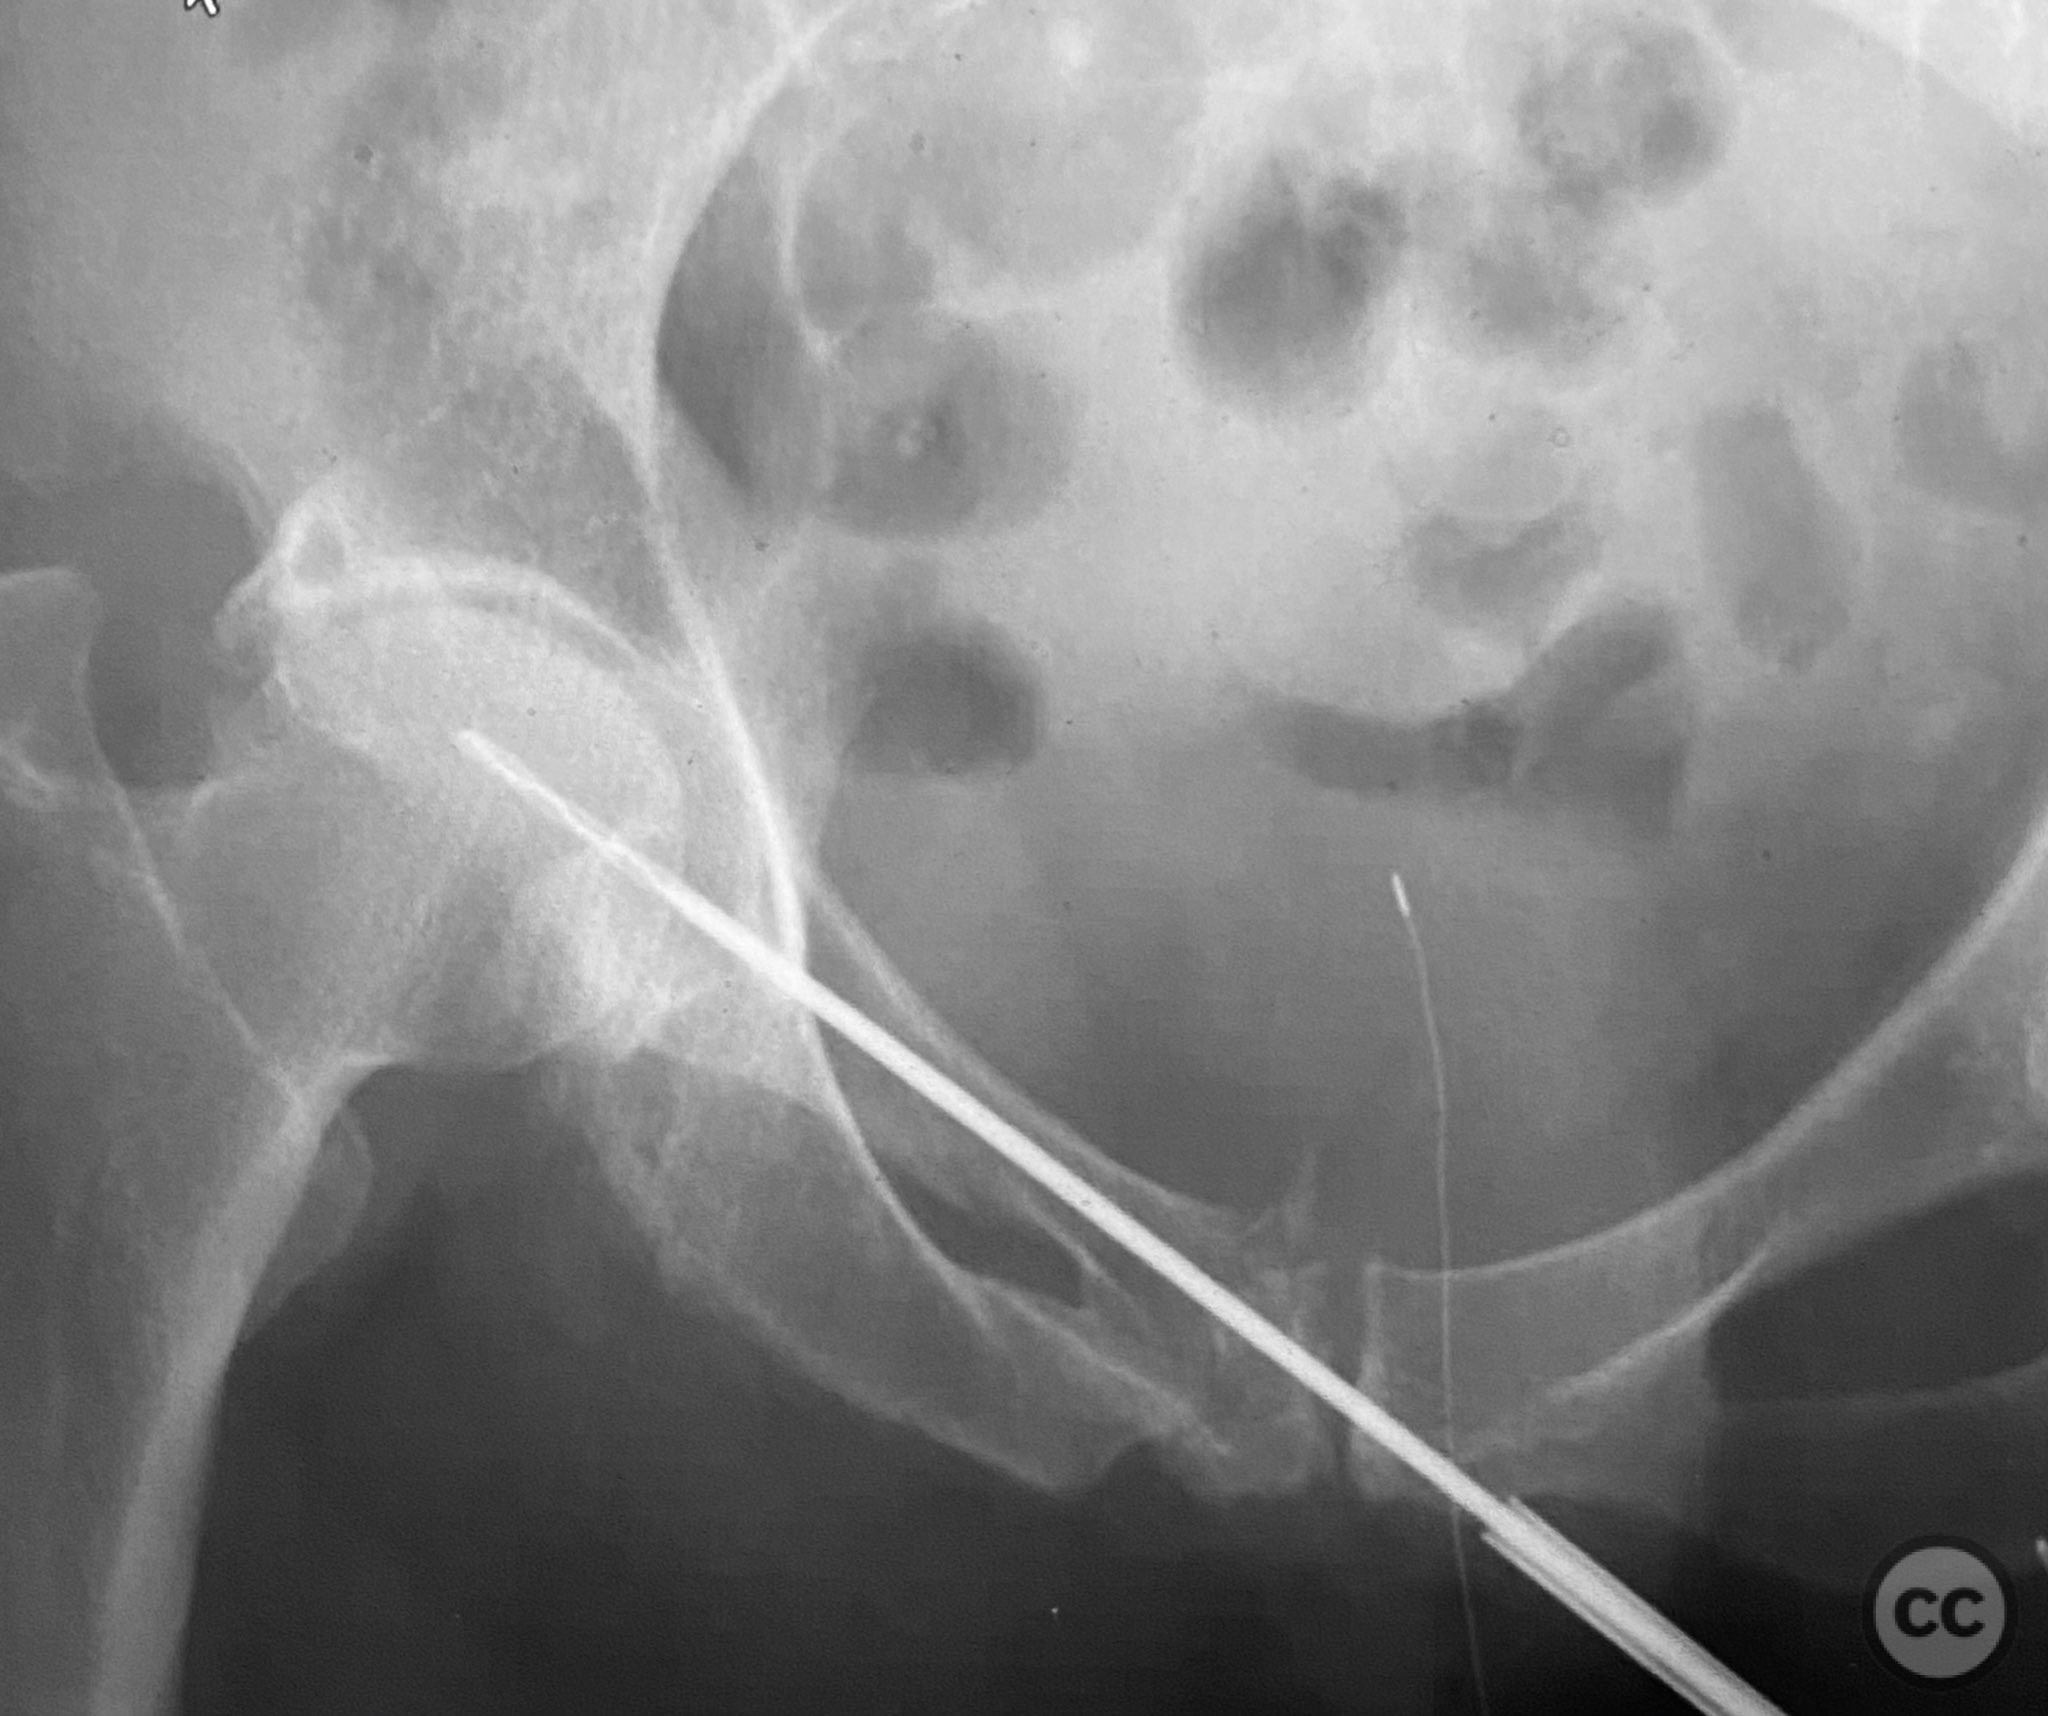

Clinical and radiological findings:  Adult patient presenting with severe pelvic pain, unable to sit or transfer to a chair. Clinical examination under anesthesia demonstrated pelvic instability with “rebound reduction” upon minimal iliac crest compression. Imaging revealed an unstable superior pubic ramus fracture with challenging anterior pelvic bone anatomy and dense cortical bone at the anterior acetabular wall.

Planning remarks:  Planned trans-symphyseal fixation of the superior pubic ramus fracture using a 4.5mm cortical screw, with preoperative intent to maximize implant purchase in stable bone regions. Surgical approach selected to facilitate direct access to the superior pubic ramus and symphysis pubis.

Intraoperatively, a 3.5mm drill was used through a protective sleeve to initiate the screw pathway across the superior pubic ramus. Due to poor bone quality, a 2.5mm drill was subsequently employed; however, resistance was encountered as the drill tip engaged the dense cortical apex of the anterior acetabular wall. The drill became lodged in this region. To avoid drill breakage, manual extraction using pliers was considered; however, the surgeon elected to carefully deflect and advance the drill manually, successfully completing the pathway. Screw length was measured directly from the embedded drill tip. A 4.5mm cortical screw was then inserted trans-symphyseally along the prepared medullary canal, achieving stabilization of the unstable ramus fracture. Postoperative CT confirmed appropriate screw trajectory and demonstrated the dense cortical bone at the anterior acetabular wall where the drill tip had engaged.